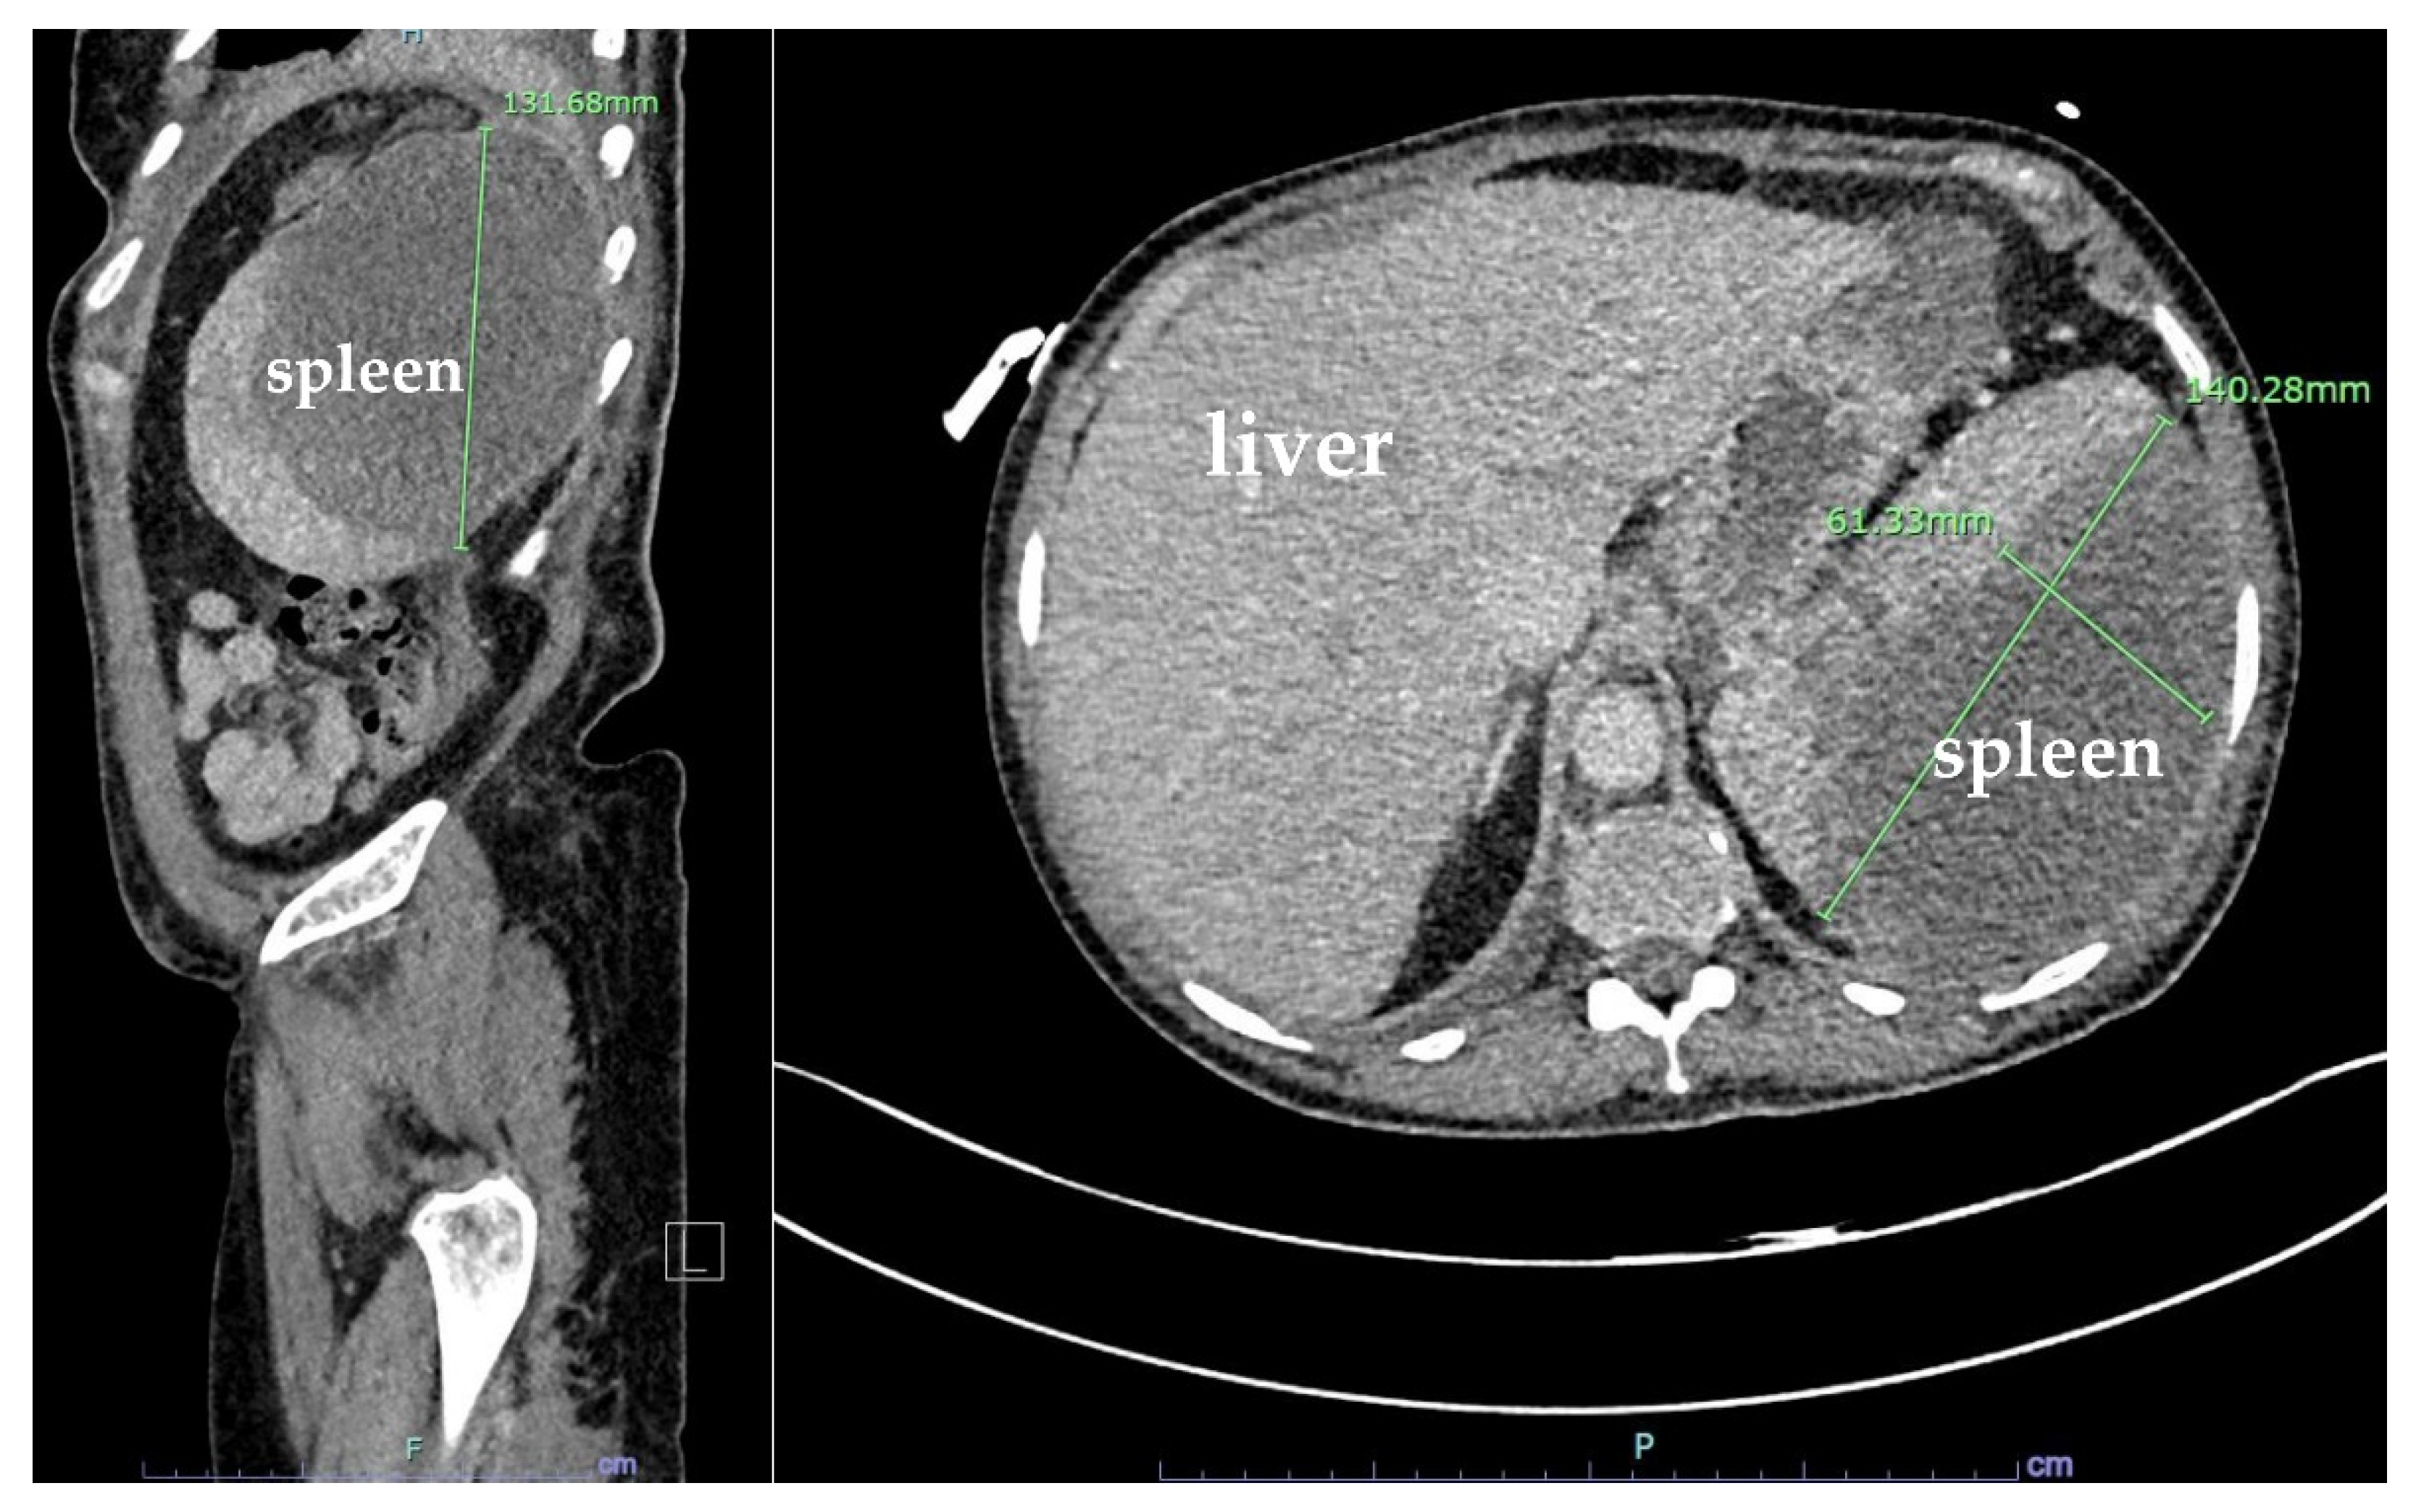

The CT angiography (CTA) of the abdomen and pelvis was negative for active bleeding. The patient was discharged 9 days after the stabilization of anemia and the resolution of her nausea and vomiting. However, she returned to the hospital 15 days later due to a syncopal episode and persistence of her abdominal pain. During that admission, she was hypotensive and was found to have anemia with hemoglobin of 6.9 g/dL that required another transfusion of one unit of packed RBCs. Repeated CT of the abdomen and pelvis showed large mixed-density splenic subcapsular hematoma of unclear etiology, which had significantly increased in size since the prior study, this time measuring 13.6 × 13.8 × 4 cm (previously 12 × 11 × 0.1 cm), with a mass effect on the splenic parenchyma and an increase in the moderate-volume hemoperitoneum (Figure 4).

Figure 4. Coronal and sagittal plane computed tomography (CT) scans with IV contrast of the abdomen and pelvis showing large mixed-density splenic subcapsular hematoma of unclear etiology, which significantly increased in size since the prior study, this time measuring 13.8 × 13.6 × 4 cm (previously 13.2 cm in greatest dimension), with a mass effect on the splenic parenchyma and an increase in the moderate-volume hemoperitoneum.